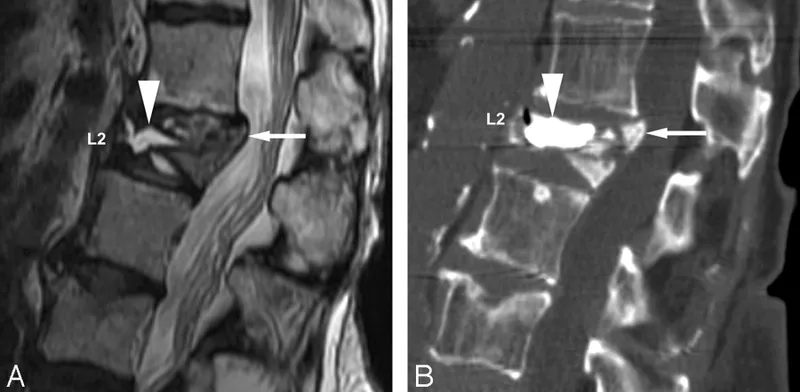

- CT Scan: Gold standard for evaluating bony anatomy, alignment, and fracture patterns.

- MRI: Essential for assessing soft tissues: spinal cord, ligaments, intervertebral discs, and hematomas.

⭐ MRI is mandatory with any neurological deficit, as it uniquely visualizes the spinal cord, ligaments, and hematomas, which can be missed on CT.